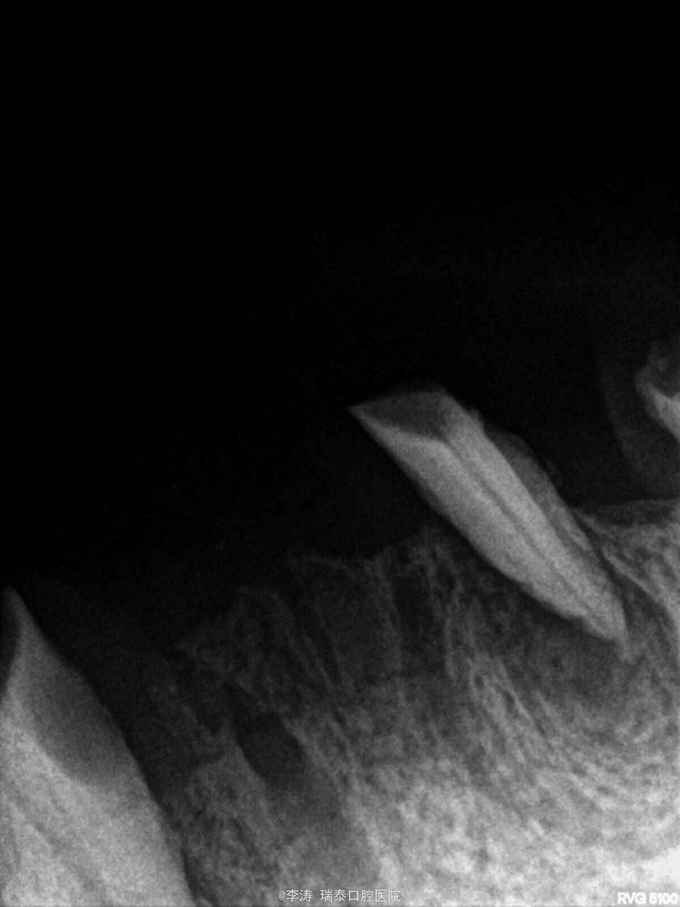

全口大部分牙缺失,上頜4~4残根,下颌32,34,34,36,37,43残根。大部分残根根尖暗影明显。除24,36,43松动III度外其余牙根均不松动

对于覆盖义齿下面的残根,多长的残根有保留价值?多大的暗影应该拔除,书上都没有明确的标准,所以想问一下各位,想14这么短的牙根的保留价值如何,还是该直接拔掉?它现在一点都不松动?